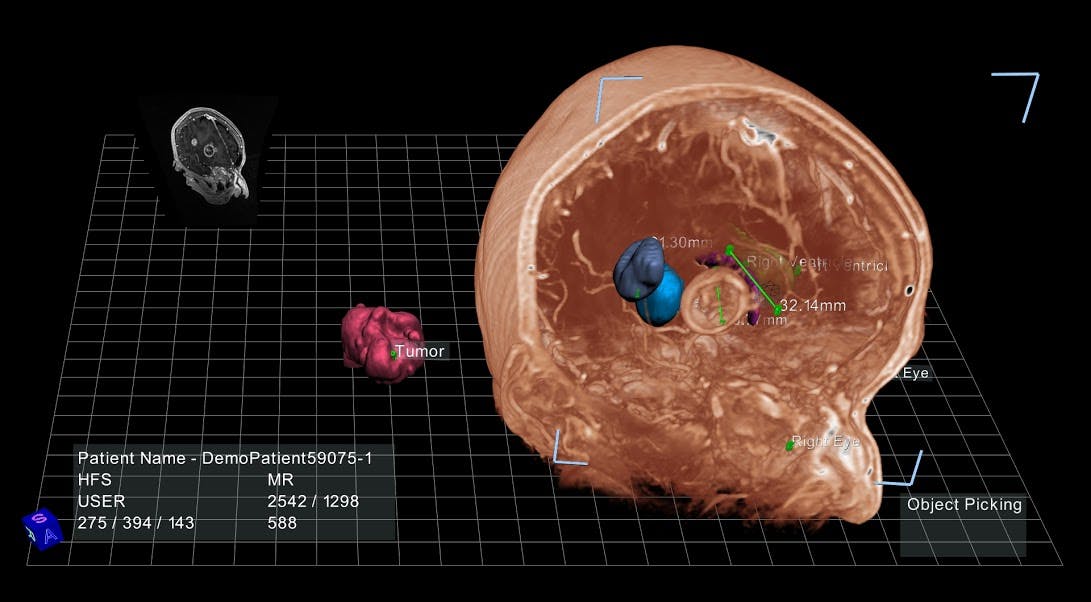

The software can transform data from ultrasound, CT, and MRI scans into three-dimensional anatomical models projected onto a computer screen, with which doctors can interact using a stylus. A doctor can, for example, click on one brightly colored segment of the virtual colon to scan the interior tissue for soft, spongy polyps, or point and click to extract an aneurysm from deep inside a virtual brain.

Doctors can also use these virtual models to create surgical plans without excessive exploratory slicing and dicing. Such plans are still essentially drawn up on a sheet of paper, which can only offer so much insight about a patient’s actual anatomy. It would be much more simple, Aguirre said, if a surgeon could have a sense of precisely how far they’ll have to reach inside a child’s chest cavity to rebuild a detached pulmonary artery.

And it could prove equally useful for training medical students, who struggle to square the flat images they see in textbooks with the real anatomy of their patients. “A liver surgeon at UCSF said, ‘I want this workstation outside the surgical suite, and I want every surgical resident to go through this model five or 10 times before they go into the operating room,’” said Ron Schilling, Ph.D., EchoPixel’s CEO.

Aguirre and Dr. Schilling hope that this software will eventually be compatible with any device with a screen, including smartphones and tablets, to facilitate quick data-sharing between doctors. The platform could even be used to help patients better understand a difficult diagnosis or upcoming surgical procedure. But most computers aren’t equipped to process 3D visualizations, so for now the software is tethered to the workstation’s high-resolution screen, which is manufactured by zSpace, a firm that specializes in holographic imaging displays.